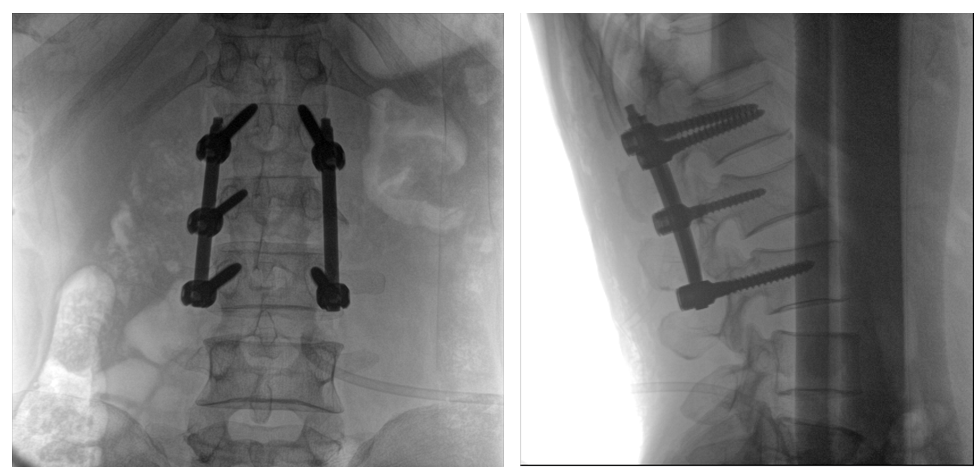

普愛醫(yī)療PLX119C大平板一體式C形臂采用30CM×30CM的平板探測器,在脊柱和長骨骨折等骨科手術(shù)治療中,獲取更大視野、更清晰的骨折部位圖像,能夠有助于醫(yī)生在術(shù)中及時了解和評估骨折部位的對位、對線情況,且能進行長度和角度測量,為進一步提高手術(shù)質(zhì)量提供強有力的支持。